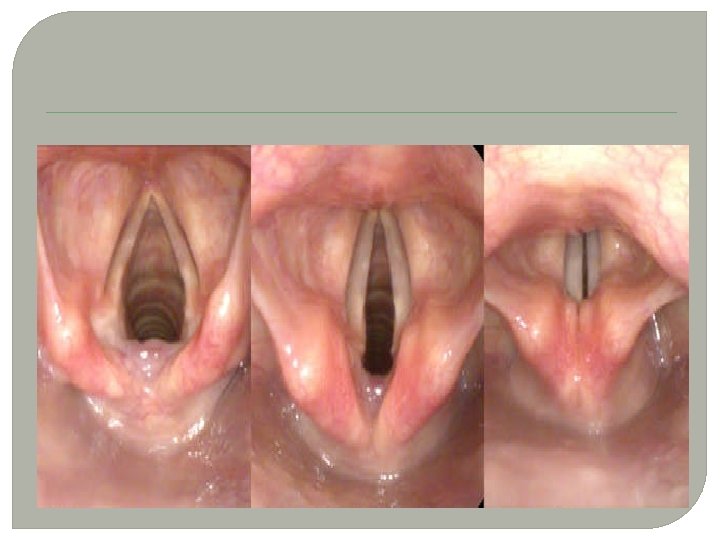

SESİN OLUŞUMU �SES TELLERİ: Ses telleri gırtlak yapısının içerisinde 3 tabakadan oluşan bir yapıdır. (kas yapısı, jölemsi yapı ve ses sinirleri) �Nefes alıp verme esnasında akciğerlerden gelen havanın, gırtlakta bulunan ses tellerinin arasından geçerken titreştirmesi sonucu oluşan titreşimlerdir.

� 2 - LARENJİT İLTİHAPLANMASI) (GIRTLAK �Ses kısılması ve ileriki safha ses kaybı �Boğaz da devamlı yanma, boğazda bir cisim varmış hissi, sürekli boğazda gıcık �En belirgin özelliği “Ses Kısılması” �TEDAVİ �Buhar solunmalı, sıvı içecekler, �Sigara bırakılmalı,

NODÜL �Ses telleri iltihabı( sesin HATALI ve YOĞUN kullanımından kaynaklanan ses telleri üzerinde nasırımsı yapı) �En önemli ses hastalığıdır. !!!! �TEDAVİ: �İlaç tedavisi yanında bitkisel tedavi �Son çare Ameliyat.

�DİĞER SES HASTALIKLARI �Ses kistleri �Polipler �Ses felçleri

POLİP RAHATSIZLIĞI